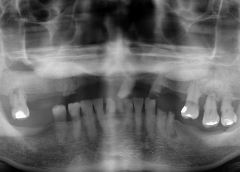

• Tình trạng mất răng:Mất răng R12 đến R27. Mất răng R32, R33, R35, R36. Nhiều răng bị sâu và có những miếng trám lớn.

• Phương hướng điều trị:Phục hồi toàn bộ răng mất bằng 10 trụ Implant và bọc lại răng sứ từ răng số 13 đến số 17.

Trong một thời gian dài, chú Minh Thiện không thể thưởng thức trọn vẹn được bữa cơm ngon. Bởi cả hàm răng đau nhức, nhiều răng bị mất hoặc sâu nặng. Dù dùng hàm tháo lắp cũng không thể cải thiện được.

Cho đến khi chú quyết định làm Implant, mới có lại được hàm răng chắc khỏe, ăn uống ngon lành trong mọi bữa cơm cùng gia đình.